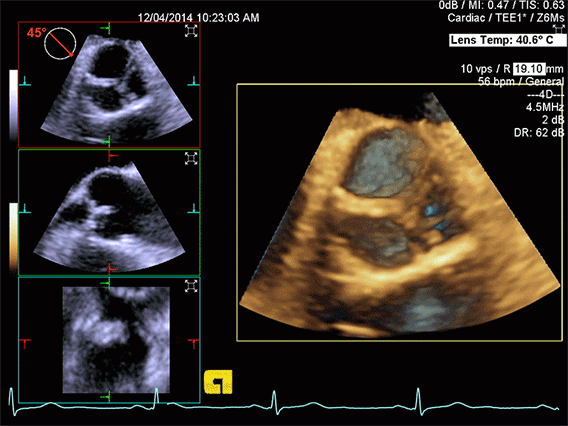

Volume Color Doppler

Mitral Valve Model with Volume Color Doppler

Volume Color Doppler of Mitral Valve